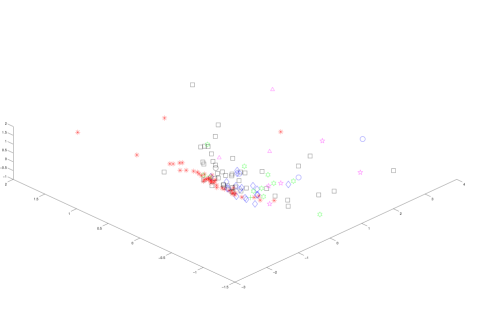

For the purpose of building intuition, we used classical multidimensional scaling (CMDS) on the distance matrix, using the above feature vectors as columns, to produce 2D and 3D visualizations of the lesions, shown in Figure 6. Note that the axes simply give the coordinates of the embedding given by CMDS and that the vertical axis in Figure 6(b) is pointed at the reader in Figure 6(a).